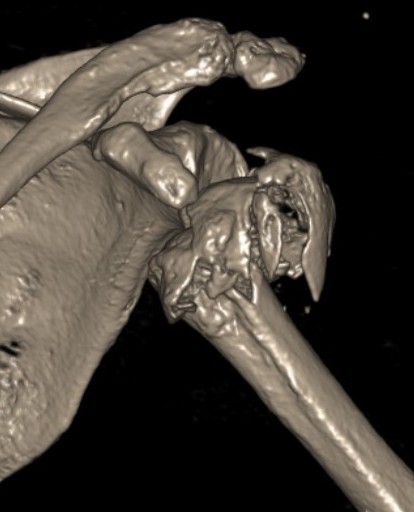

Severe comminuted proximal humerus fractures

100% displaced / off ended

Fracture - dislocations

- comminuted, 3 or 4 part

- head spltting fracture

- off ended / 100% displaced

Unreconstructable fracture - 4 part, comminuted, head spltting fracture